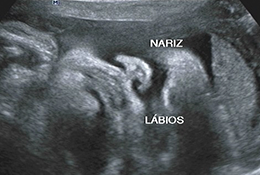

Com alta tecnologia realizamos diversos tipos de ultrassonografias: Obstétrica, Obstétrica com Doppler, Morfológica, 4D, Transvaginal, Transvaginal para pesquisa de Endometriose, Abdominal, Mamas, Tireoide e outros.